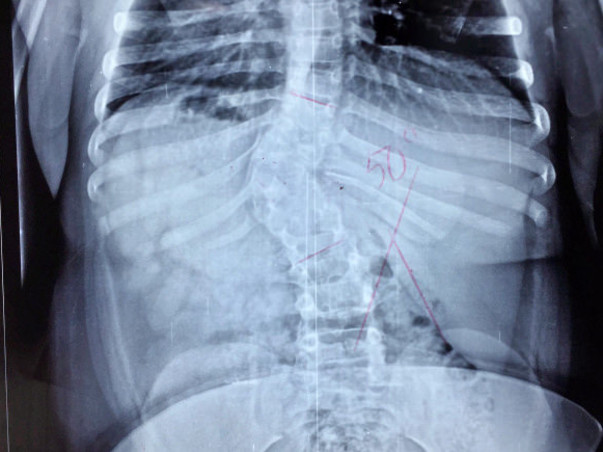

Life was very normal for Shivani except for the fact that her growth was not proper. Her parents didn’t bother about her height much thinking, it will be fine as she grows up. It was only when the younger brother grew taller than her, the parents realised that there is something wrong with her. Shivani was taken to a local hospital where they got the shock of her life. An MRI report revealed Shivani was suffering from a severe spinal cord deformity. According to doctors, Shivani has to undergo a corrective surgery or else her arm and limbs will be paralysed.